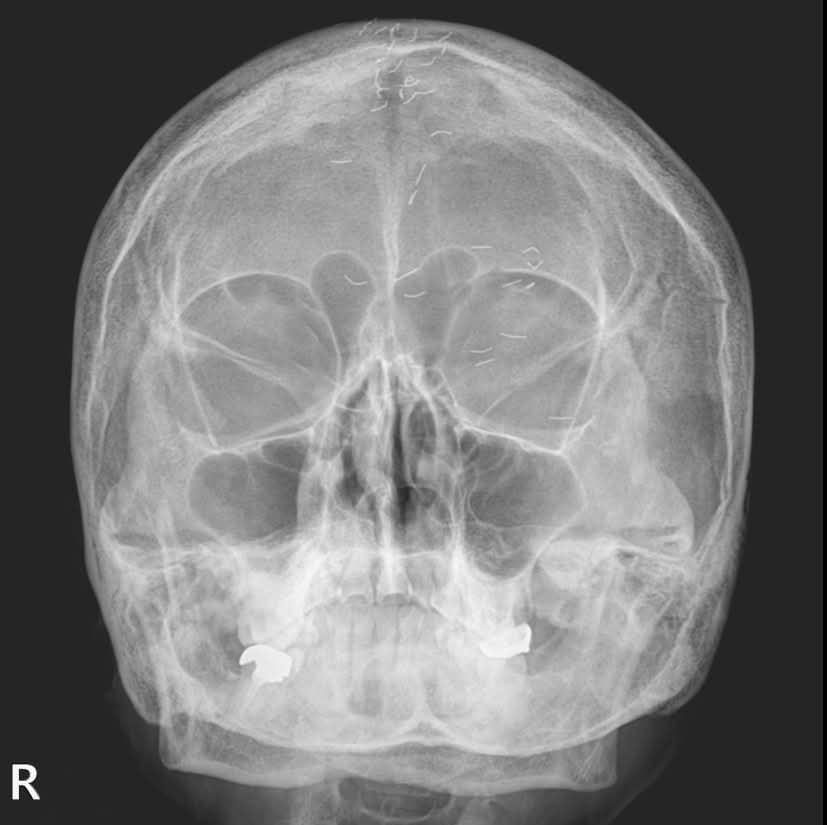

두통 호소한 60대 여성 머릿속 가득한 기생충 '모양'…정체는 '금침'